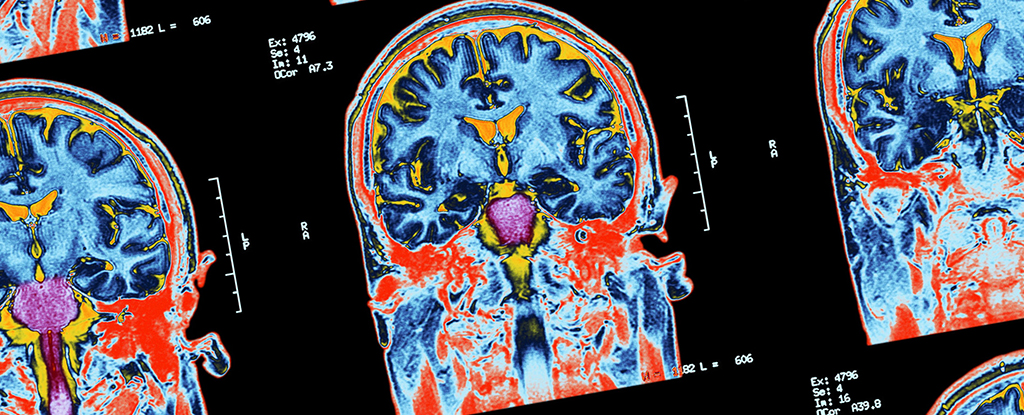

In the new study, signs of consciousness were found through fMRI (functional magnetic resonance imaging) and EEG (electroencephalography) brain scans in 60 out of 241 patients tested, after being given instructions such as “imagine opening and closing your hand”.